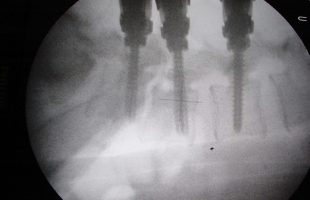

Περίπτωση: Ιω. Ζο. – Εκρηκτικό κάταγμα σπονδυλικής στήλης (Σφαίρα) – Χειρουργική αντιμετώπιση

Ο Ιω. Ζο. 60 ετών το 2009 υπέστη εκρηκτικό κάταγμα του 1ου οσφυικου σπονδύλου συνεπεία τυχαίου πυροβολισμού. Συνέπεια αυτού ήταν να εγκατασταθεί πλήρης κινητικο-αισθητική παραπληγία κάτωθεν του επιπέδου της βλάβης. Ο τραυματίας υποβλήθηκε σε χειρουργική επέμβαση (χ.ε.) αλλαχού για αποσυμπίεση του νωτιαίου μυελού από τα παρεκτοπισθέντα οστικά τεμάχια και σταθεροποίηση της σπονδυλικής στήλης. Περαιτέρω ο